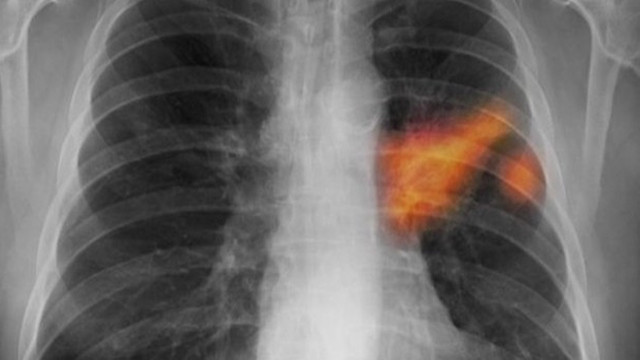

Bu durum bronşlarda salgılanan mukusun miktarını arttırarak bronş duvarlarında kasılmaya neden olur. Tıbbi adı pruritus olan kaşıntı uykusuzluğa gerginliğe ve depresyona bile neden olabilir. Akciğer damarlarında çeşitli nedenlerden kaynaklı olarak hava baloncukları yağ topları kan pıhtıları gibi tıkanıklıkların gelişmesi ve tıkanıklığa neden olan bu pıhtıların dolaşım sistemine etki etmesine tıbbi olarak pulmoner embolizm ya da halk arasında akciğere pıhtı atması denir. Yün kimyasal maddeler sabunlar ve diğer maddeler cildi tahriş edebilir ve kaşınmaya neden olabilir.

Egzama gibi deri hastalıkları gıda kaynaklı alerjiler mantar enfeksiyonları parazitler şeker hastalığı isilik kurdeşen ve hormonal sorunlar kaşıntıya neden olabilir. Bir de psikolojik ve bilişsel etkenler. Solunum sistemi üzerindeki damarlarda şişmeye neden olan kronik bir hastalıktır. Akciğerde yanma hissine neden olan bazı hastalıklar ve diğer belirtileri şöyle sayılabilir.